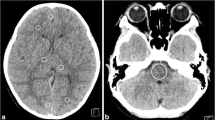

We calculated the angular differences in the FLB–CTV line between the I-123 IMP SPECT and the CTAC images in the same patient, using an angle measurement tool in the Xeleris Functional Imaging Workstation (GE Healthcare) on midsagittal images obtained with I-123 IMP. Following which, we investigated whether these I-123 IMP SPECT images could be used to set the FLB–CTV line. The FLB–CTV line of each patient was measured by a radiology technician with 13 years of experience in nuclear medicine examination (Fig. 2). Furthermore, the inter-reader reproducibility of the FLB–CTV line measurements on the I-123 IMP SPECT images in the cohort of 50 patients was evaluated for two readers (reader 1: radiology technician with 13 years of experience, 5 years of nuclear medicine examination experience; reader 2: radiology technician with 4 years of experience, but no nuclear medicine examination experience).

The FLB–CTV line on each image. a The FLB–CTV line on the I-123 IMP SPECT image. b The FLB–CTV line on the CTAC image. CTAC computed tomography attenuation correction, FLB–CTV frontal lobe bottom and cerebellum tuber vermis, I-123 IMP SPECT iodine-123 isopropyl iodoamphetamine single-photon emission computed tomography

The mean ± standard deviation of the angular differences in the FLB–CTV line between the I-123 IMP SPECT and the CTAC images was 0.87° ± 0.48° (range: 0°–2°). Additionally, the ICC of the FLB–CTV line measurements on the I-123 IMP SPECT images was 0.99 (95% CI: 0.98–0.99) (Fig. 3).